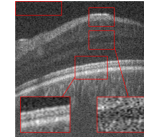

The effect of the overlap of the patches on the final output of the algorithm has been investigated in the next simulation. For this purpose, the outputs of the proposed approach for the situations and have been compared. When , the patches have no overlap. The resulting higher resolution OCT images for each situation have been illustrated in Fig. 8. Visual comparison in addition to the PSNR and SSIM for each image, show that using patches with overlap, we can increase the performance of the algorithm and consequently improve the quality of the output image.

Reference image

Using patches without overlap

Using patches with overlap